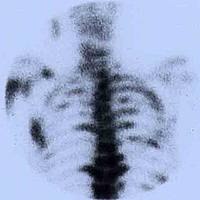

Knochenmetastasen

Nuklearmedizinische Schmerzbehandlung

Seit einigen Jahren bietet die Klinik für Radiologie, Interventionelle Radiologie und Nuklearmedizin auch die nuklearmedizinische Schmerzbehandlung bei Knochenmetastasen, insbesondere bei Prostata- und Brustkrebs an.

• Radionuklidtherapie

Die Radionuklidtherapie ist ein (palliativer) Baustein in der Behandlung dieser fortgeschrittenen Krankheitsform. In der Regel wird die Behandlung zwischen Urologen und Nuklearmedizinern abgestimmt.